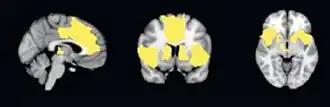

Kerngebieden van het SN zijn de cortex cingularis anterior, de presupplementaire motorische schors en de insula anterior. De insula fungeert in het netwerk als een centraal kernelement of hub met een regulerende functie.